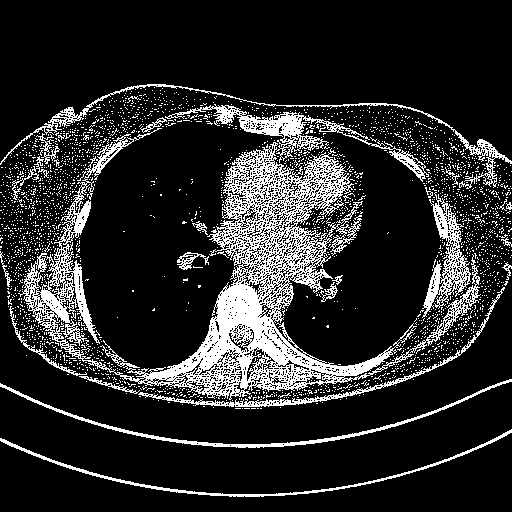

Generated VENOUS CT scan (A→B translation)

Full window (WL 1023.5, WW 4095 β†’ Low βˆ’1024, High +3071)

Actual HU range: [-1024.0, 3071.0]